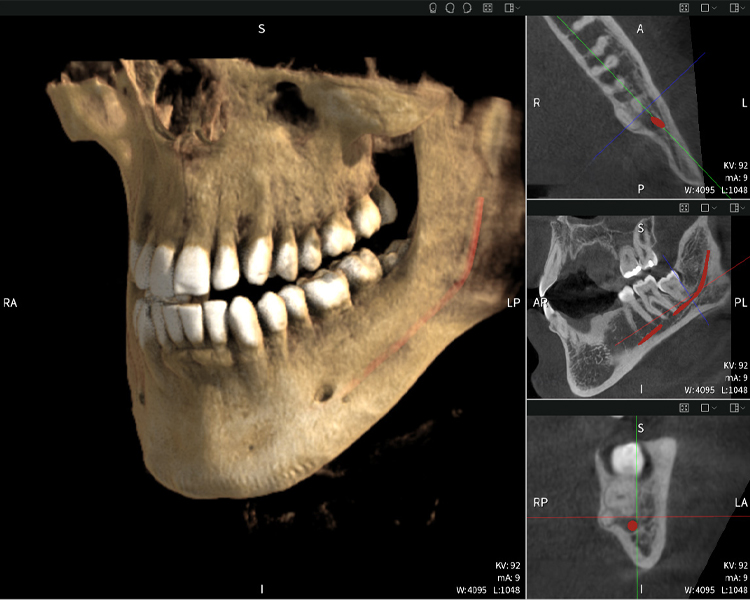

Abbildungen b–d zeigen verschiedene Ansichten einer 3D-Rekonstruktion des Unterkiefers und bieten eine umfassende Übersicht über die Anatomie des Unterkiefers, die Lage der Nerven im Verhältnis zu den Zähnen und ermöglichen die Beurteilung der Zahnsymmetrie und Ausrichtung.

Abbildung d zeigt den bereits vorbehandelte Zahn 48, dessen Krone entfernt wurde und dessen Wurzeln nahe am Nerv belassen wurden, was das hohe Risiko einer Nervenschädigung verdeutlicht.

Abbildung e: Panoramaröntgenaufnahme dient der initialen Beurteilung und zeigt die allgemeine Zahnstellung sowie mögliche pathologische Veränderungen auf. Insbesondere ist auf der rechten Seite (Zahn 48) die Situation nach einer Kronenamputation durch einen externen Behandler ersichtlich. Die beiden stark gekrümmten Wurzeln verbleiben in enger topographischer Beziehung zum Nervus alveolaris inferior im Knochen. Dies deutet auf eine bewusste Entscheidung zur Vermeidung eines erhöhten Risikos einer Nervenläsion während einer vollständigen Extraktion hin und stellt einen klinisch relevanten Befund dar. Zusammenfassend liefern die CBCT-Aufnahmen mit Seethrough Max entscheidende Informationen über die komplexe Anatomie und die kritische Beziehung zwischen den Weisheitszähnen und dem Nervus alveolaris inferior. Diese detaillierte präoperative Diagnostik ist unerlässlich für die sichere und erfolgreiche Durchführung chirurgischer Eingriffe im Unterkieferbereich.